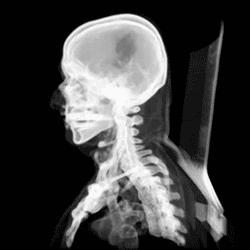

Че́реп (лат. cranium) — костная или хрящевая часть головы[1][2] у позвоночных животных, каркас головы, защищающий от повреждения наиболее уязвимые органы и служащий местом прикрепления её мягких тканей. Он поддерживает структуры лица и создает защитную полость для головного мозга и хорошо защищённые глазницы для глаз[3].

Череп состоит из двух отделов: висцерального (лицевого) и мозгового (черепная коробка). Причём у человека, в отличие от животных, мозговой череп значительно преобладает над лицевым. Все кости черепа, кроме нижней челюсти и подъязычной кости[6], соединены неподвижным соединением[7].

Считается, что человеческий череп состоит из двадцати двух костей — шести костей мозгового черепа и девяти костей лицевого скелета. В нейрокраниуме это затылочная кость (лат. os occipitale), две височные кости (лат. os temporale), две теменные кости (лат. os parietale), клиновидная (лат. os sphenoidale), решётчатая (лат. os ethmoidale) и лобная кости (лат. os frontale)

Костями лицевого черепа являются сошник (лат. os vomer), две нижних носовой раковины (лат. concha nasalis inferior), две носовых кости, две челюсти: пара верхнечелюстных костей (лат. maxilla), одна нижняя челюсть (лат. mandibula), две небные кости (лат. os palatinum), две скуловых кости (лат. os zygomaticum), и две кости слёзных (лат. os lacrimale). Некоторые источники включают подъязычную кость (лат. os hyoideum)[6] или три косточки среднего уха, но в целом общее мнение о количестве костей в человеческом черепе двадцать три, включая подъязычную.